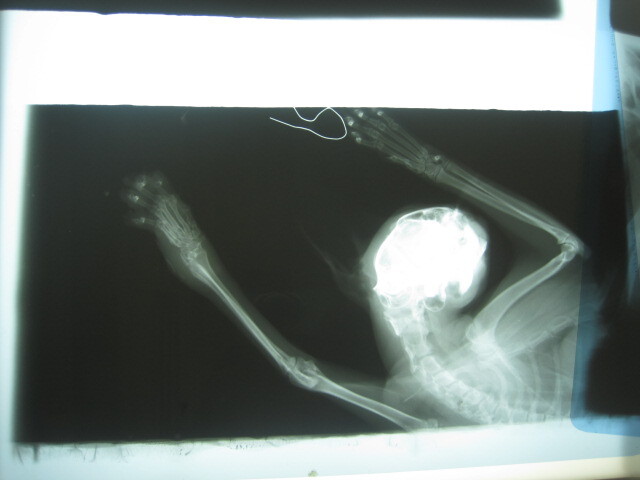

- 編號: 2622

主題: 左腕關節腫脹 有50元硬幣大的外傷 申請者姓名: 張慧敏 花色: 申請日期: 2013-06-20 16:27:53 申請者部落格: 申請者臉書網址: 所在縣市/合作醫院: 台北市/詠欣動物醫院 治療費用: 5700元 需求人數: 13人 已結案 (2013-08-06 14:28:47) 報名人員: davidlai(已付款)、Lynn、Liwing Lin(已付款)、Josephine(已付款)、Josephine(已付款)、Josephine(已付款)、Stephy An(已付款)、惠惠(已付款)、蔡餅乾(已付款)、Linda x4(已付款)、喵喵(已付款)、 候補人員: 黃安妮、RuRu Liu、 動物病情說明: 捕捉結紮發現左腕關節腫脹、有50元硬幣大的外傷,現已經復原R回,醫療費用還請各位幫忙